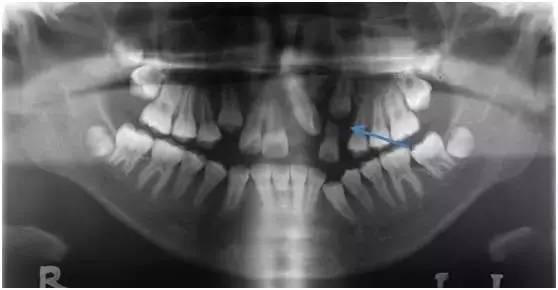

含牙囊肿

含牙囊肿内充满液体,并且随着时间的推移会逐渐增大,造成进展式骨破坏及损伤邻牙牙根(如图蓝色箭头处)。牙根受损的牙齿越到后期,往往难以治疗,甚至不得不拔除。

图:左上中切牙及尖牙的含牙囊肿

造成骨质缺失, 左上侧切牙牙根吸收

所以一旦发现含牙囊肿要及时手术刮除,并尽快将牙齿牵引助萌,避免囊肿复发。